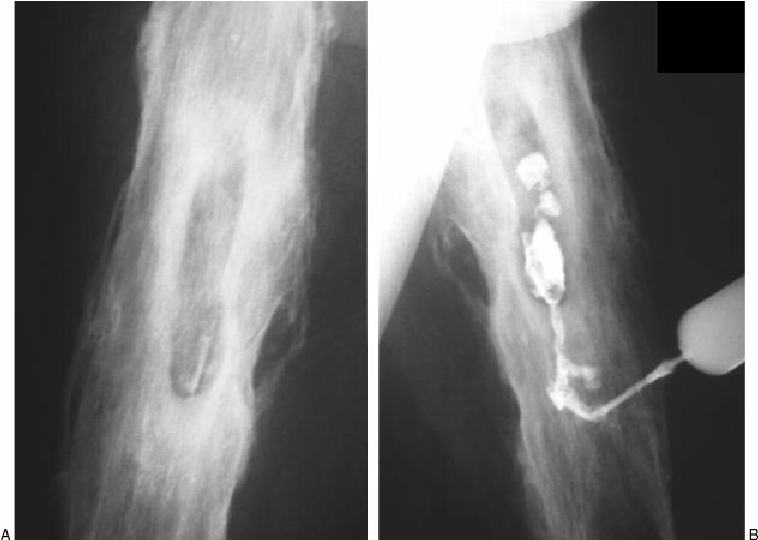

Level of amputation:

2. Lower limbs:

g. Very short below knee,

h. Short and below knee.

Level of amputation in details:

Below the knee: below the knee amputation preserve the knee joint and make prosthetic fitting and amputation easier

Above knee: Above the knee amputation do not preserve the knee, they are usually performed for trauma or PVD..